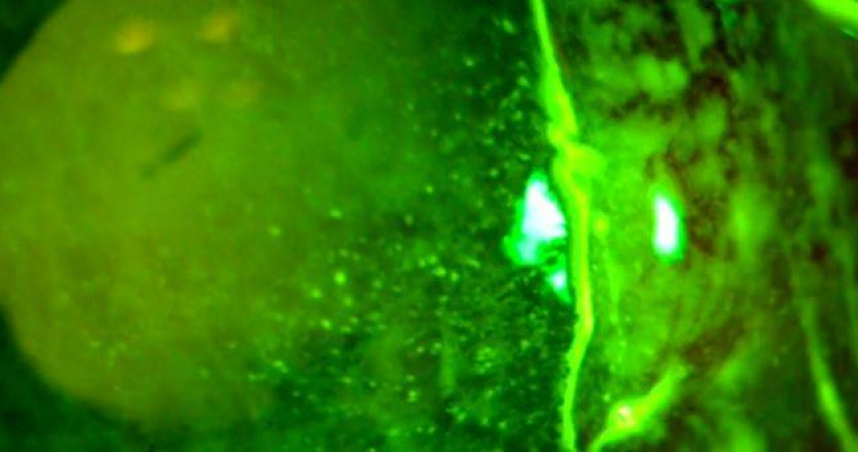

角膜

感染